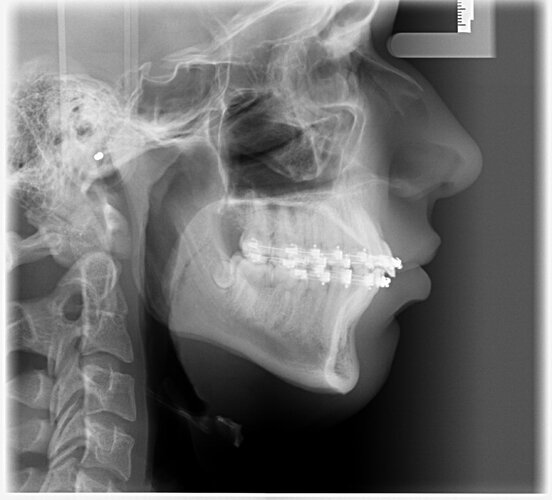

I had Bimaxsurgery + genioplasty yesterday performed by Dr Dr Kater, Frankfurt am Main, Germany. I'm 17 and it went well, no nerves are botched and he told me the Plan was executed perfectly fine. In the pictures you can see 24h before and 24h after the surgery. He did a great job with my maxilla and mandible but the genioplasty is slightly underadvanced. My nose had a very big glowup but it'll all look different in 5 months i'm very bloated rn. What do yall think?

Mirin, ur nose bump is already gone I also have similar case like u and also have short face syndrome but am confuse if getting CW rotation will make me more recessed, in ur x ray i can see u wont have a major change in ur face apart from ur nose bump, ramus and chin , i think u will need more osteotomy to get the perfect length of the bone just like LL surgery where they increase ur bone length everyday. Honestly am not aware abt this i will have to research myself abt that cuz gettin a CW rotation will do more harm to face than good it make ur face long and recessed

i had a very very very minimal cw, not optimal for forward growth but there's hardly any surgeon in germany that does cw and i had short face syndrome so it would't ascend me that much. my nose lips and chin look far better i can already see my ramus through the swelling, i'm very happy, but youre right: I didn't get that much sagittal movement, still a good bimax tho

Lower jaw and chin look Under advanced as expected from a krautcel surgeon.

whats the point of surgery if he still looks recessed, shouldve got bigger movements